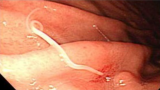

- これが魚に寄生するアニサキス(『厚生労働省オフィシャルホームページ』より)

- 胃に寄生するアニサキス(『厚生労働省オフィシャルホームページ』より)